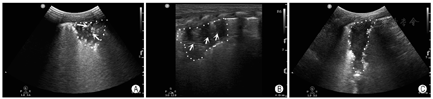

沙滩征:M型模式扫查,可见由胸膜线上方波浪线样的线性高回声与胸膜线下方由肺滑动产生的均匀颗粒样点状回声共同形成类似沙滩样表现的超声影像(图5)。

应观察是否存在胸膜线异常(光滑、连续性)、B线(数目及分布)、实变(范围、支气管充气征)、胸腔积液(性质)、气胸等。B线、肺泡间质综合征与白肺(图7)三种声像图表现反映肺内含水量由轻到重的程度。

B线:起始于胸膜线并与之垂直,呈放射状纵向发散至肺野深部的线性高回声。

肺泡间质综合征:当任一扫描区域内有连续两个以上肋间隙存在融合B线时。

白肺:如果两侧肺的每个扫描区域均表现为致密B线即为白肺。